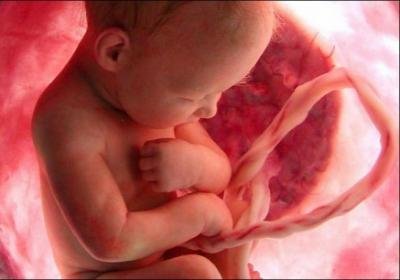

На двенадцатой недели плод становится настолько хорошим, что усовершенствоваться остается только маленьким деталям. Все органы и системы у плода ужу сформировались и начали свою активную работу. У ребенка